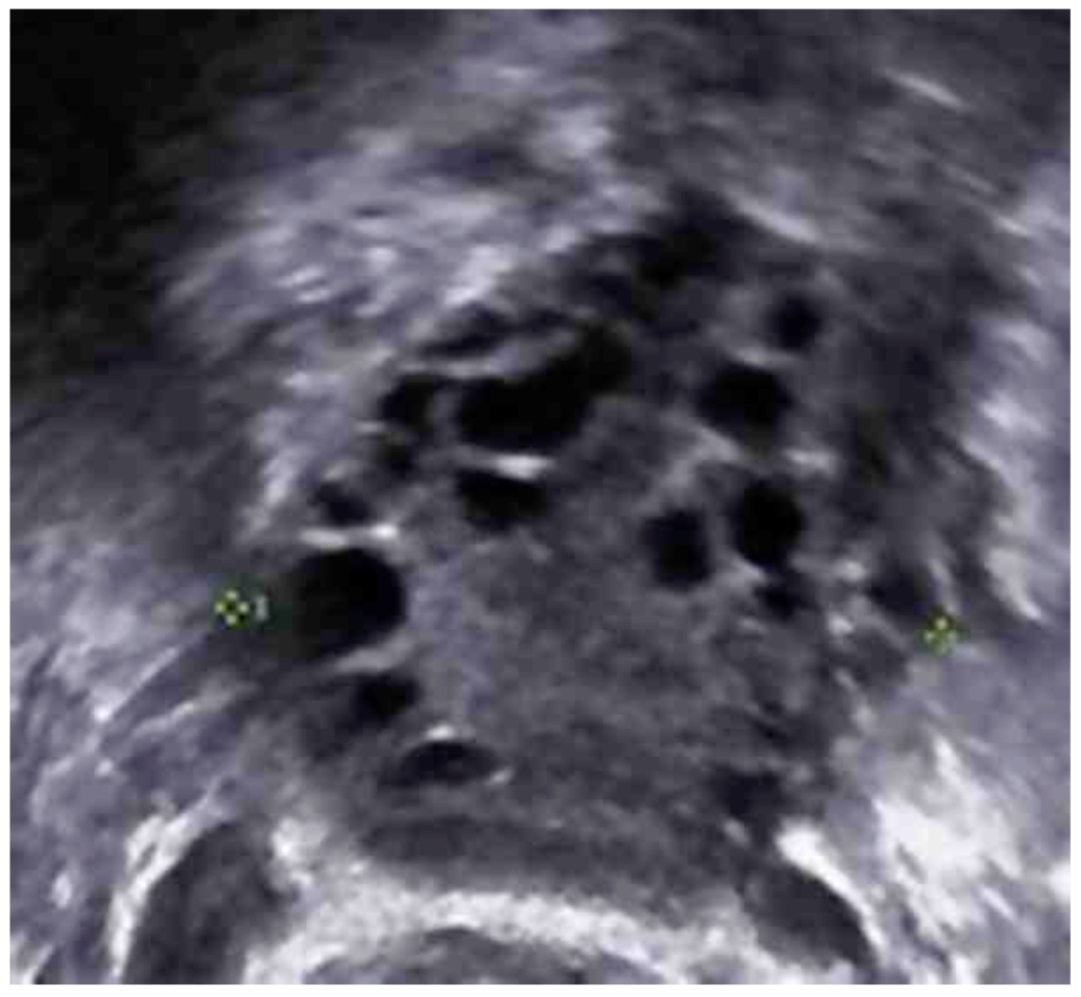

36세 산과력 0-0-0-0인 여자가 4개월 전부터 월경을 하지 않는다며 병원에 왔다. 평소 월경주기는 60~ 90일로 불규칙 하였다. 12년 전부터 하루 평균 담배를 한 갑 정도 피운다고 한다. 키 160 cm, 체중 78 kg이다. 혈압 135/85 mmHg, 맥박 78회/분, 호흡 20/분, 체온 36.6°C이다. 외음부, 하복부 및 허벅지 안쪽에 털이 많다. 검사 결과는 다음과 같다. 오른쪽 난소의 초음파검사 사진이다. 치료는?

US: Polycystic ovary

US 상 polycystic ovary가 있으므로 해당 US 소견, 희발월경, 고안드로겐증을 통해 PCOS로 진단한다.

• US: 다낭성 난소 소견